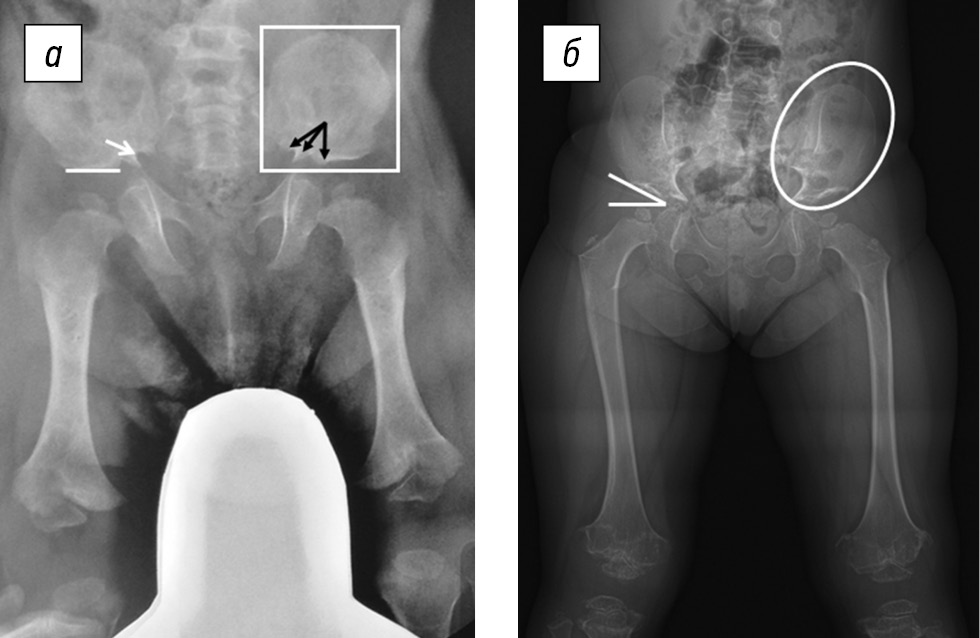

Характерные признаки на рентгенограммах, позволяющие проводить подтверждающую диагностику АХ у детей раннего возраста, включали квадратную форму крыльев подвздошной кости, плоскую горизонтальную вертлужную впадину, узкую седалищную вырезку, сужение междужкового расстояния в поясничном отделе позвоночника, короткие трубчатые кости с умеренным метафизарным расширением, рентгенопрозрачность проксимального отдела бедренной кости, брахидактилию с рентгенологической картиной симптома трезубца (рис. 4). В основе этого рентгенологического симптома лежит особенность оссификации надацетабулярной области, в результатом чего формируются «зубцы». Три «зубца», образованных кортикальным слоем седалищной вырезки, контурами оссифицированной части подвздошной кости и сводом вертлужной впадины, видны на рентгенограммах.

Рис. 4. Рентгенограммы тазобедренных суставов и бедренных костей в прямой проекции пациентов с ахондроплазией (а) и псевдоахондроплазией (б): а — горизонтальное положение свода вертлужной впадины (белая линия), суженная седалищная вырезка (белая стрелка), симптом трезубца (черные стрелки), квадратные очертания крыльев подвздошных костей (белый контур); б — скошенность свода вертлужной впадины (белые линии), овальные очертания крыльев подвздошных костей (белый контур)